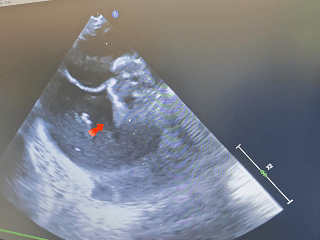

双封堵器释放后超声

出院前超声

超声所见:

心脏位于左侧胸腔,心尖指向左下。房室连接正常。右心较术前减小。左室壁不增厚,运动未见明显异常。主动脉瓣形态结构未见异常;二尖瓣形态结构未见异常;三尖瓣形态结构未见异常。

CDFI:AR(-),MR(少量),TR(少量)。房间隔中部探及两处封堵器回声,房水平未见明显分流。室间隔连续完整,室水平未见明显分流。肺动脉内径不增宽。升主动脉内径23mm。心包腔内未见明显液性暗区。

TDI:E’:0.08m/s,A’:0.06m/s。

《常见先天性心脏病介入治疗中国专家共识》指出:对于存在2个ASD,但缺损间距≤7mm,可选择1枚封堵器闭合;多个缺损的间距>7mm,无法采用1枚封堵器实施介入治疗,需要选择2~3枚封堵器分别闭合[1]。本例食道超声示两处缺损(回声中断8.06mm,分流束宽5.63mm),两个缺损之间相距8.48mm,术中通过超声精准指导,先植入BDASD-I16封堵器封堵8.06mm缺损,再测量第二个缺损约5mm后,植入BDASD-I10封堵器,术后即刻超声显示,两枚MemoSorb可降解封堵器位置形态理想,无残余分流,封堵成功。

术后患者恢复顺利,胸闷气短症状显著改善,复查心脏超声提示封堵器位置稳定、无残余分流,右室负荷减轻,心脏功能指标(如舒张功能)趋向好转。该病例验证了可降解封堵器在双孔型房缺治疗中的临床价值——既克服了多发缺损定位与封堵的技术难点,又通过“短期有效、长期无害”的特性,为患者提供了更安全、可持续的治疗方案。